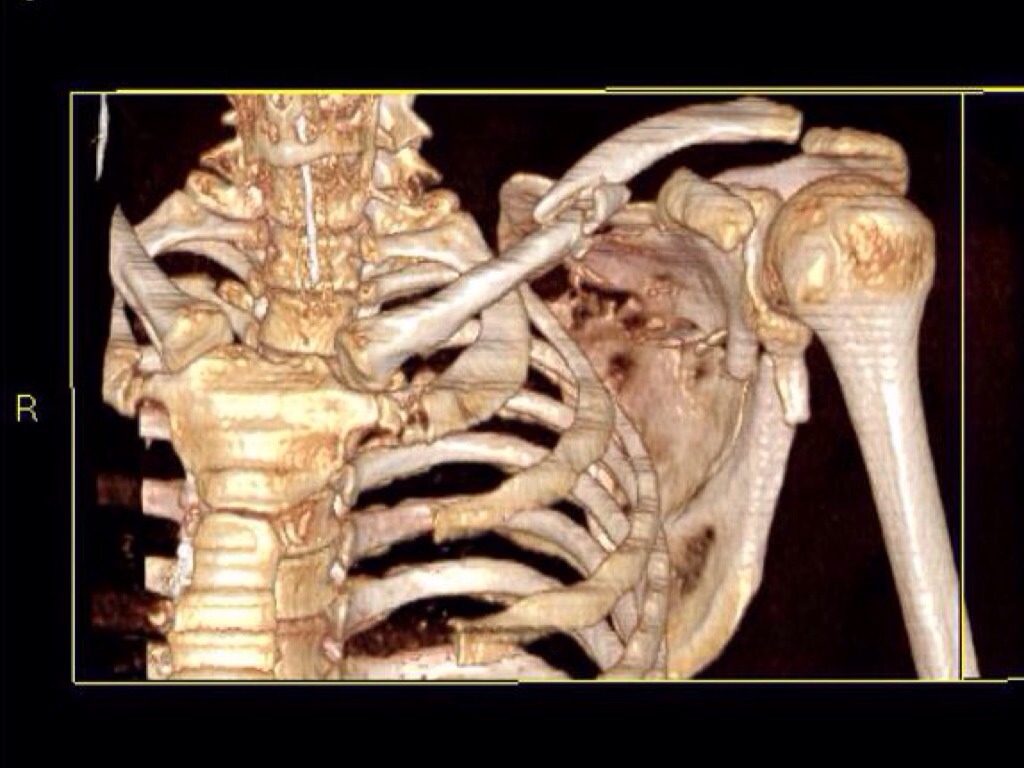

Radiology Career Information for Younger Students

BASIC SKILLS IN ANATOMY, BIOLOGY,PHYSICS, AND MATH